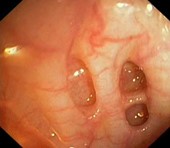

Дивертикула |